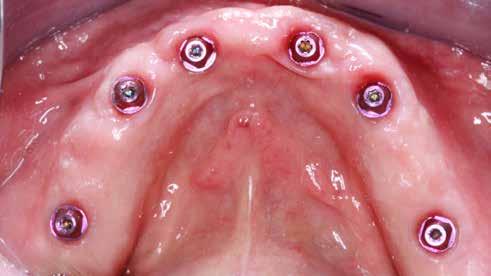

Ebben a cikkben egy 16 éves lánypáciens esetét szeretném bemutatni (1–7. képek)

A Pitts21-es fix készülékes kezelés során a harapásemelőket a felső nagyőrlő fogakra ragasztottuk, hogy a felső molárisok intrúziójával segítsék a harapás zárását (8. kép) Ún. keresztharapásos, majd később normál class 2-es gumihúzással (9–10. képek), továbbá az elülső fogakon alkalmazott ún. Rainbow harapás-záró gumihúzással (11. kép) korrigáltuk a jobb oldali teljes premolárisnyi distal-harapást, valamint az elülső nyitott harapást.